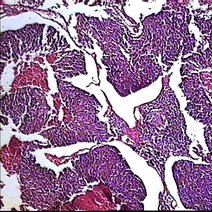

结直肠癌

结直肠癌,常见的消化道恶性肿瘤,发生率仅次于胃癌和食道癌。在我国常见恶性肿瘤死亡中,结直肠癌患者在男性占第五位,女性占第六位。近二十年来结直肠癌的发病率在逐渐增加,同时,其发病年龄...